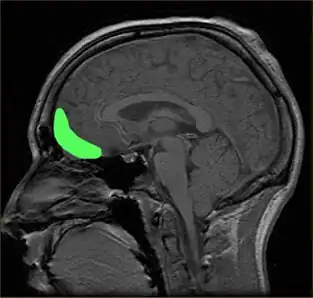

Although the precise neural mechanisms underlying disorders of impulse control are not fully known, the prefrontal cortex (PFC) is the brain region most ubiquitously implicated in impulsivity.[150] Damage to the prefrontal cortex has been associated with difficulties preparing to act, switching between response alternatives, and inhibiting inappropriate responses.[144] Recent research has uncovered additional regions of interest, as well as highlighted particular subregions of the PFC, that can be tied to performance in specific behavioral tasks.

Excitotoxic lesions in the nucleus accumbens core have been shown to increase preference for the smaller, immediate reward, whereas lesions to the nucleus accumbens shell have had no observable effect. Additionally, lesions of the basolateral amygdala, a region tied closely to the PFC, negatively affect impulsive choice similarly to what is observed in the nucleus accumbens core lesions.[106] Moreover, dorsal striatum may also be involved in impulsive choice in an intricate manner.[151]

Go/No-go and Stop-signal reaction time test

The orbitofrontal cortex is now thought to play a role in disinhibiting,[152] and injury to other brain structures, such as to the right inferior frontal gyrus, a specific subregion of the PFC, has been associated with deficits in stop-signal inhibition.[153]

As with delay discounting, lesion studies have implicated the core region of the nucleus accumbens in response inhibition for both DRL and 5-CSRTT. Premature responses in the 5-CSRTT may also be modulated by other systems within the ventral striatum. In the 5-CSRTT, lesions of the anterior cingulate cortex have been shown to increase impulsive responding, and lesions to the prelimbic cortex impair attentional performance.[154]